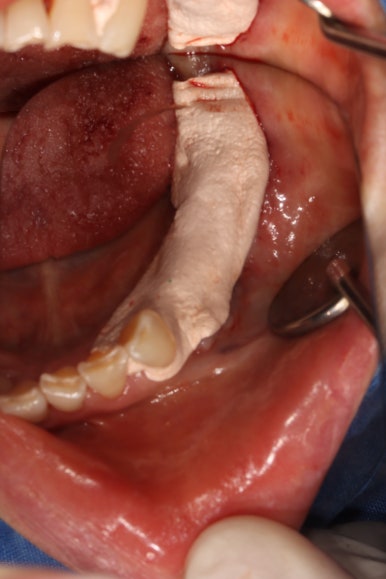

먼저 부분층 판막 (partial thickness flap)을 예쁘게 형성하여,

골막이 드러나는 환경을 만들어 줍니다.

원하는 크기를 선택하여 치유지대주를 연결해 줍니다.

부분층 판막을 형성하였기 때문에, 사실 가만히 두면 부착치은이 되어 회복될 것입니다만

어떤 퀄리티로 치유가 완성될지 모르는 불명확한 상황이므로 유리치은이식술이 최고입니다.

앞서 보셨던 제 논문과도 같이,

골막 상방에 입천장에서 채득한 두께 1mm의 얇은 유리치은을 이용하여 유리치은이식술을 시행해줍니다.

많이 꿰매지 않기 때문에 시간이 오래걸리지는 않아요.

잇몸이식수술이 완료되고 나면, 수술 부위를 보호하기 위해 치주팩을 설치해줍니다.